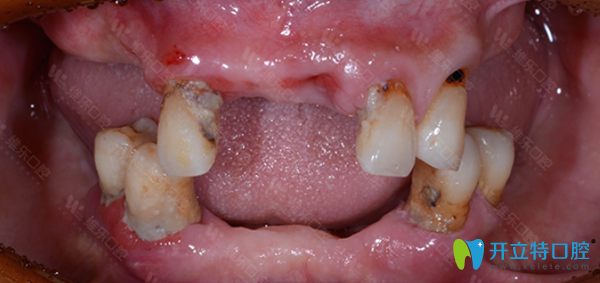

姓名:王先生 年齡:62歲

口腔問(wèn)題:牙齒脫落,牙槽骨脆弱,沒(méi)有牙營(yíng)養(yǎng)吸收低,整個(gè)人渾身無(wú)力。

主治醫(yī)師:翟建博 MAXI數(shù)字化疑難種植中心主任。

治療方案:全口種植。

種牙前,王大爺飽受缺牙帶來(lái)的種種折磨。經(jīng)翟建博主任仔細(xì)檢查后,建議采用數(shù)字化即刻負(fù)重種植牙技術(shù),來(lái)修復(fù)王大爺缺失的牙齒。